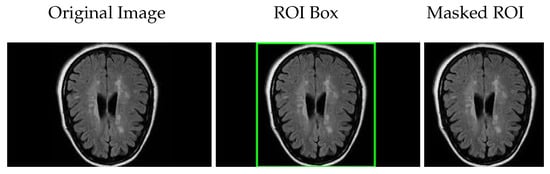

In the preprocessing phase, the first step involves identifying the region of interest (ROI) within the brain MRI images to focus subsequent analysis on relevant anatomical areas. This step helps exclude irrelevant regions, improving the accuracy and efficiency of the classification process.

To locate the ROI, we applied several image processing techniques. First, image enhancement was performed by adjusting contrast and brightness and applying smoothing filters to reduce noise, as described in [21]. Then, Otsu’s thresholding method was used to binarize the image, effectively separating the brain tissue from the background. Following this, contour detection was carried out [22], identifying the boundaries of significant anatomical structures.

Based on the detected contours, bounding boxes were generated to localize the ROI within the image. Subsequently, a mask was applied to the original brain MRI scan to isolate the targeted region by covering non-essential areas. This process reduces background noise and focuses the classification algorithms on the relevant brain region, such as the prefrontal cortex or hippocampus.

Figure 3 illustrates these steps: the original brain scan, the ROI highlighted by a bounding box, and the final masked ROI extracted for further analysis.

This targeted approach not only improves computational efficiency but also enhances the effectiveness of the downstream classification models by restricting their focus to meaningful image regions, as discussed in [23].

Figure 3. Brain region localization: original brain scan, ROI marked with a bounding box, and the extracted region using a mask.